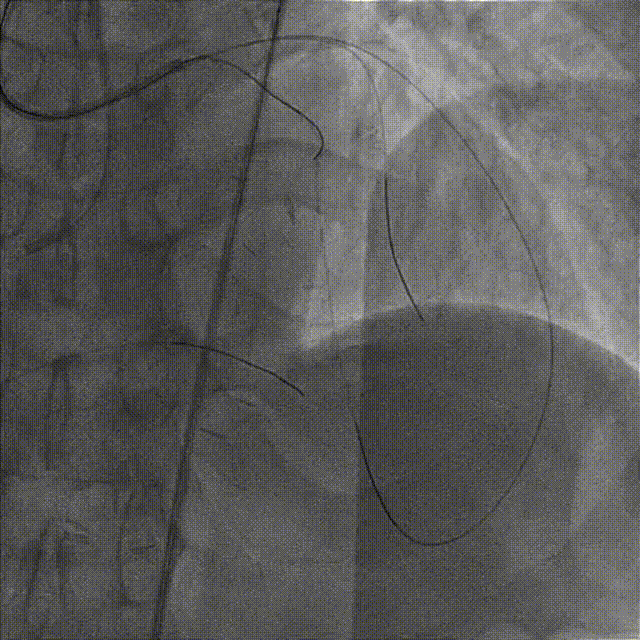

造影示支架定位良好,D1开口受压90%狭窄,交换一根SION导丝穿支架网眼至D1远段,用Pinoeer1.5mm x 15mm、Pinoeer 2.0mm x 15mm球囊至D1开口处扩张。

FOXTROT NC 2.5mm x 15mm、FOXTROT 3.0 mm x 15mm后扩球囊后扩球囊至支架内后扩,以实现支架的充分贴壁,并对LAD远段进行球囊扩张,造影显示TIMI血流III级。

术后行IVUS检查示:支架定位贴壁扩张良好,LAD开口MSA:7.43mm2。